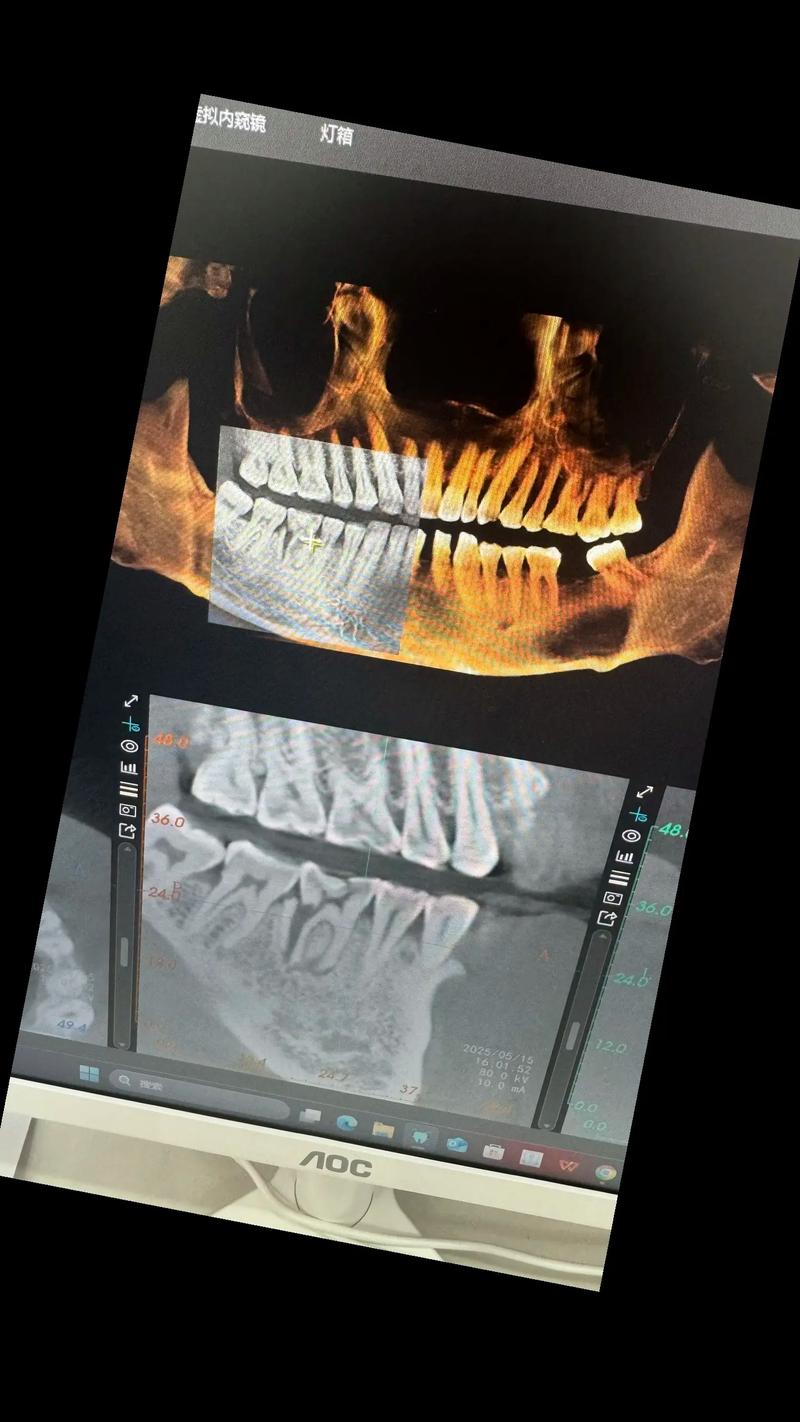

若牙根已无法保留(如完全折断、吸收或感染),种植牙的核心前提是牙槽骨条件是否允许,牙根是维持牙槽骨量的关键,牙根脱位或拔除后,牙槽骨会逐渐发生“废用性萎缩”,吸收速度在拔除后前3个月最快,每年可能吸收0.5-1mm,若吸收过多,会导致牙槽骨宽度、高度不足,无法支撑种植体,此时需要先进行“植骨手术”,通过自体骨(如从下颌骨取骨)、人工骨(如羟基磷灰石)或异体骨填充骨缺损,等待3-6个月骨结合完成后,再进行种植手术,牙根摔掉后能否种牙,第一步需通过CBCT(锥形束CT)等影像学检查评估牙槽骨的骨量,判断是否需要植骨及植骨的可行性。

种植牙手术本身是成熟的微创治疗,流程通常包括:术前检查(口腔检查、CBCT、血常规等)→种植体植入(在局麻下将钛合金种植体植入牙槽骨)→骨结合期(3-6个月,种植体与牙槽骨融合)→基台连接(安装愈合基台,牙龈成形)→牙冠修复(制作并安装个性化牙冠),整个过程中,患者可能感受到轻微肿胀或疼痛,但通常可通过药物缓解,术后保持口腔卫生、避免术区咀嚼硬食是保证成功的关键。